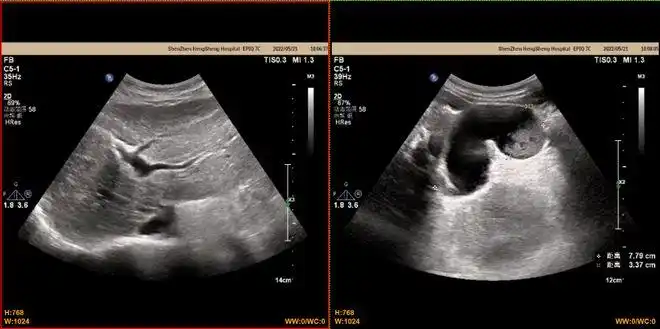

迟发性脾破裂(10月4日更正) - 超声医学讨论版 - 爱爱医医学论坛

深圳一女环卫工意外车祸致脾破裂大出血,经抢救后脱离危险